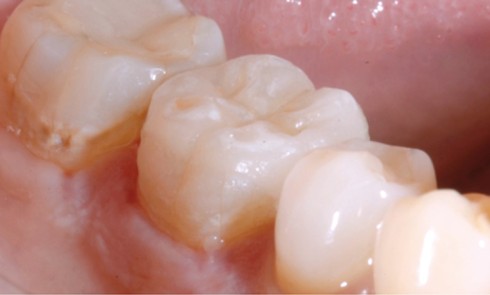

Odontologie restauratrice

Article réservé à nos abonnés L’overlay : le successeur de la couronne périphérique

La dépulpation préventive dans le but d’éviter les sensibilités postopératoires, autrefois enseignée et pratiquée couramment, est aujourd’hui assimilable à une...